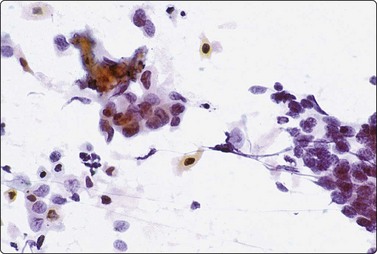

Inadvertent aspiration of the seminal vesicle may yield large atypical cells that may mislead the unwary into an erroneous diagnosis of poorly differentiated carcinoma. Large hyperchromatic, often multilobated, pleomorphic, even bizarre, nuclei are seen.9,36,37 Coarse intracytoplasmic granules of lipofuscin, which stain dark green–blue with DQ, brown with Pap or H&E, quite different from the secretory granules of prostate epithelium (Figs 13.12 and 13.13), dense aggregates of basophilic amorphous material and spermatozoa in the background indicate origin from seminal vesicle.

image

Fig. 13.12 Seminal vesicle epithelium

(A) Large bizarre nuclei; note occasional spermatozoa in the background (arrow) (DQ, HP); (B) Single epithelial cells with large pleomorphic nuclei; note coarse intracytoplasmic pigment (DQ, HP).

image image

Fig. 13.13 Seminal vesicle epithelium

(A) Vaguely glandular aggregates of epithelial cells with pleomorphic and hyperchromatic nuclei; abundant cytoplasm with vacuoles and brown pigment granules (Pap, HP); (B) Corresponding tissue section (H&E, HP).